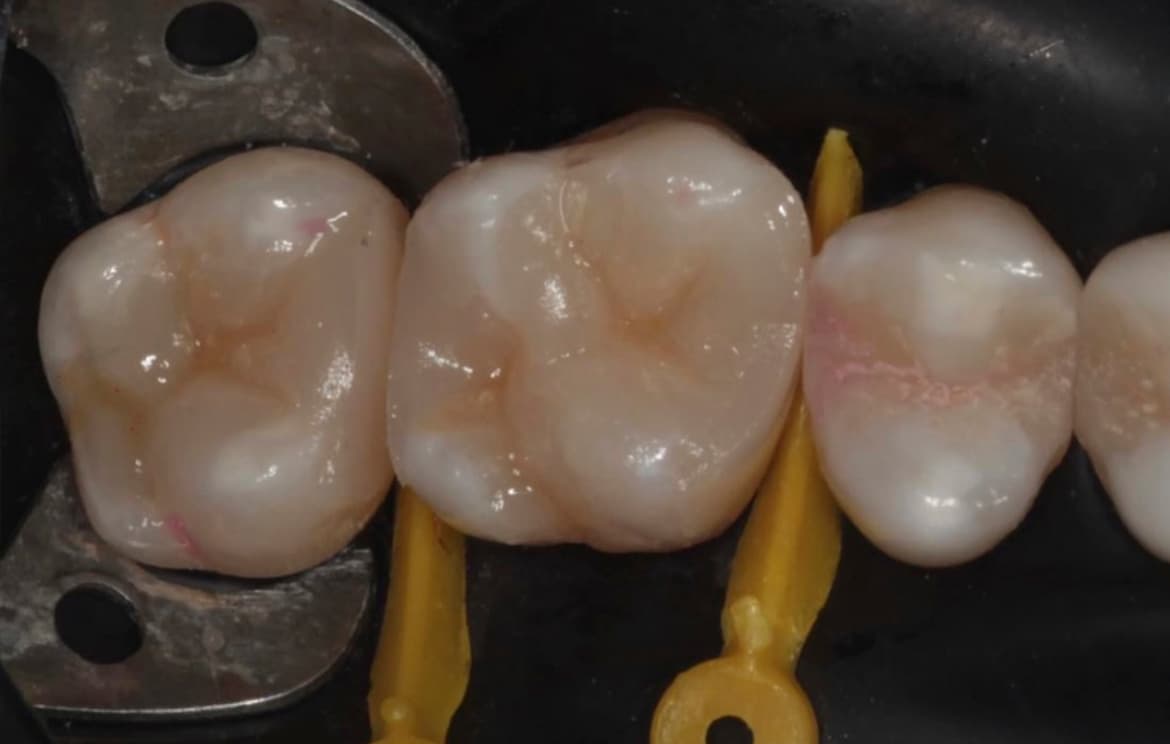

Использование биосовместимых материалов. Применение материалов, способствующих быстрому заживлению и регенерации тканей.

Наши работы